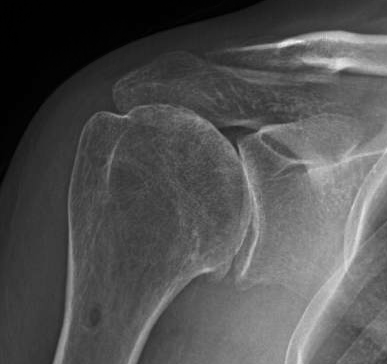

Chondrolysis [ICD Code M94.3] is the process of breakdown of cartilage. It can occur as a result of trauma (traumatic chondrolysis). Intra-articular infusions of certain local anesthetic agents such as bupivacaine, lidocaine, ropivacaine and levobupivacaine can also lead to this effect.